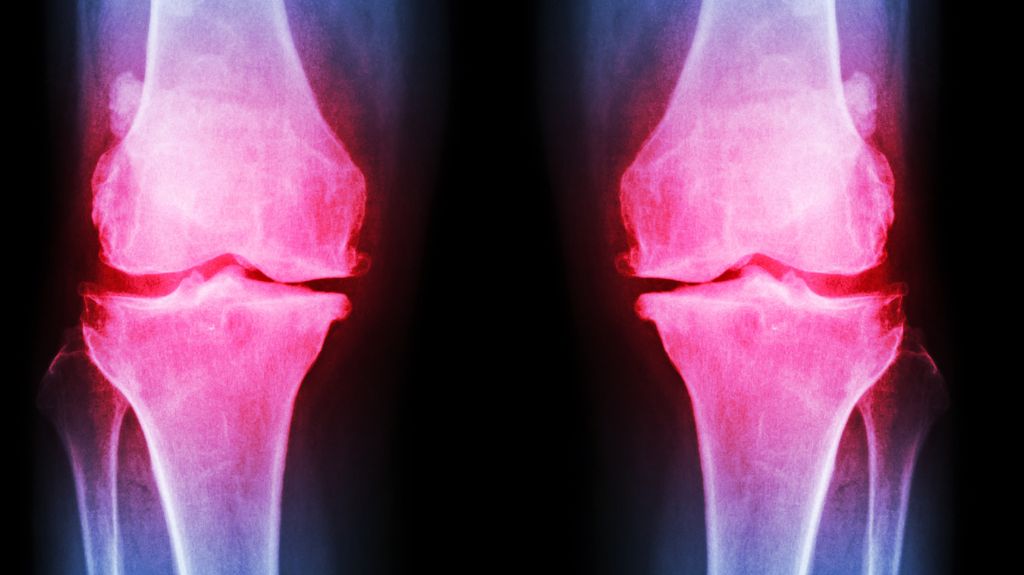

क्या आपके घुटने में भी बहुत ज्यादा दर्द होता है, अकड़न महसूस होती है, चलने फिरने में दिक्कत महसूस होता है या घुटने से चटकने की आवाज आती है। अगर हां तो यह जोड़ों के खराब होने और ऑस्टियोआर्थराइटिस विकसित होने की और संकेत करता है। ऐसे में बहुत जरूरी है कि आप इसे इग्नोर करने की बजाएं डॉक्टर से दिखाएं।

ऑस्टियोआर्थराइटिस एक प्रकार का गठिया होता है। वहीं यह समस्या आपको तब होता है जब आपके जोड़ों की रेखा बनाने वाली उपास्थि घिस जाती है या खराब हो जाती है। ऐसे में जब आप उस जोड़ का उपयोग करते हैं तो आपकी हड्डियाँ आपस में रगड़ खाती हैं। वही यह बीमारी शरीर के सभी जोड़ों से को प्रभावित कर सकती है।